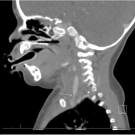

Catherine Anderson-Quinones, BM; Kinza Khan, BA; Sonal Khedkar, BS ; Andrew Wilner, MD; Jay Patel, DPM, MD

The patient was a 48-year-old man who presented with headache, left eye ptosis, a dilated pupil, and tooth pain for 10 days duration. They had a history of hypertension and poorly controlled type 2...